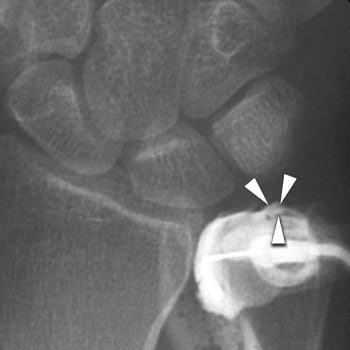

![]() |

| Coronal 3D dual-echo steady-state MR image (60/10, 20˚ flip angle) findings in same wrist (as above) confirm presence of volar SLL (arrow) and central TFC (arrowhead) tears. "Association Between Extrinsic and Intrinsic Carpal Ligament Injuries at MR Arthrography and Carpal Instability at Radiography: Initial Observations," Theumann NH, et al. Radiology 2006;238:950-957. |